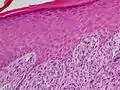

Adenoid squamous-cell carcinoma

Adenoid squamous-cell carcinoma Basaloid squamous-cell carcinoma

Basaloid squamous-cell carcinoma Clear-cell squamous-cell carcinoma

Clear-cell squamous-cell carcinoma Spindle-cell squamous-cell carcinoma

Spindle-cell squamous-cell carcinoma